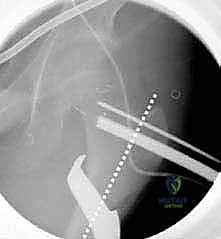

3. إدخال السلك الدليلي (Guide Wire)

تحت توجيه الأشعة السينية المباشرة داخل غرفة العمليات (C-arm)، يقوم الدكتور هطيف بإدخال سلك دليلي في عنق ورأس عظم الفخذ بالزاوية الصحيحة والمحسوبة بدقة.

6. التثبيت الداخلي القوي (Internal Fixation)

لضمان التحام العظم في وضعه الجديد، يستخدم الدكتور هطيف نظام تثبيت عالمي يتمثل في صفيحة الشفرة الزاوية (AO 90-degree Blade Plate) أو مسامير وصفيحة مخصصة للأطفال. يتم إدخال الشفرة في عنق الفخذ، وتثبيت الصفيحة على جسم العظم باستخدام براغي معدنية قوية.